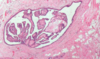

Breast abscess from acute mastitis

Acute mastitis

Acute mastitis